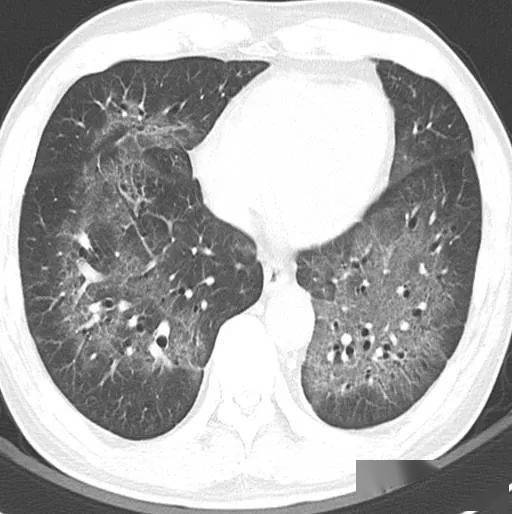

间质性肺炎的典型图谱最全解析

间质性肺炎的典型图谱 - 好大夫在线